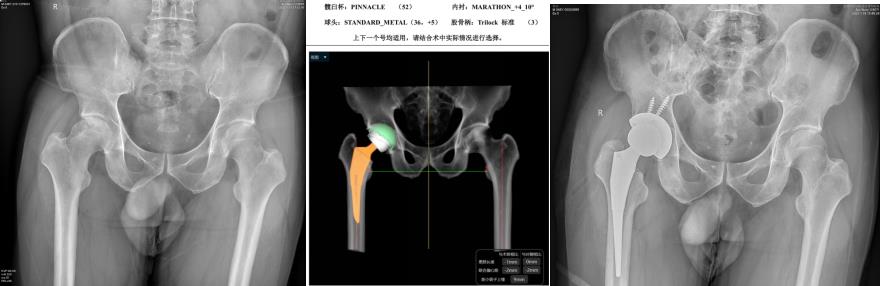

玉林市中西医结合骨科医院——骨病骨肿瘤股骨头坏死专科,是全国股骨头坏死保髋联盟成员单位,玉林市中医重点专科建设单位,是广西区内较早成立的、专注于股骨头坏死、骨病与骨肿瘤的特色科室。科室深耕上述疾病领域多年,始终恪守“精准诊疗、微创为先、中西结合”的理念,吸引了大量区内外患者慕名求医,每年开展的髋关节置换手术超千台,以精湛技术为众多患者重塑行走希望。

科室配备有专业的DAA关节置换工具、微创保髋工具、针对早期股骨头坏死的专业冲击波一体机、可用于清除骨肿瘤的超高转速磨钻等专业仪器,为病人治疗提供了强有力的硬件支持。